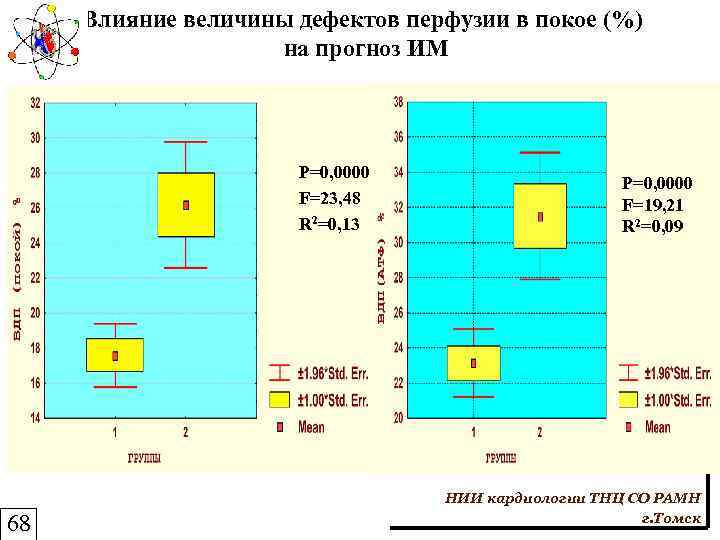

Изучение прогностической значимости ОЭКТ сердца с 99 m. Тс-технетрилом 210 Больных, через 3 -4 недели после ОИМ ОЭКТ с 99 m. Тс-технетрилом протокол "нагрузка-покой" Год наблюдения "Благоприятная" группа 138 человек "Неблагоприятная" группа 72 человека 20 - ОИМ (8 летальных исходов) 44 - нестабильная стенокардия 8 - прогрессирующая СН 67

Изучение прогностической значимости ОЭКТ сердца с 99 m. Тс-технетрилом 210 Больных, через 3 -4 недели после ОИМ ОЭКТ с 99 m. Тс-технетрилом протокол "нагрузка-покой" Год наблюдения "Благоприятная" группа 138 человек "Неблагоприятная" группа 72 человека 20 - ОИМ (8 летальных исходов) 44 - нестабильная стенокардия 8 - прогрессирующая СН 67

Влияние величины дефектов перфузии в покое (%) на прогноз ИМ P=0, 0000 F=23, 48 R 2=0, 13 68 P=0, 0000 F=19, 21 R 2=0, 09 НИИ кардиологии ТНЦ СО РАМН г. Томск

Влияние величины дефектов перфузии в покое (%) на прогноз ИМ P=0, 0000 F=23, 48 R 2=0, 13 68 P=0, 0000 F=19, 21 R 2=0, 09 НИИ кардиологии ТНЦ СО РАМН г. Томск